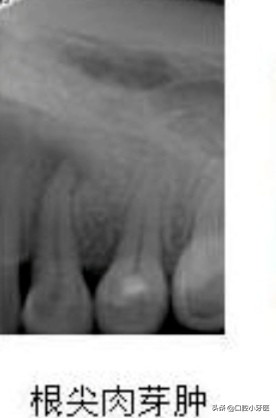

- 首先牙齿的根尖周炎最开始表现为根尖周的肉芽肿,影像即牙片上看到的肉芽肿,显示为中心为低密度区,而且病变范围要小于一个厘米,周围的边界清晰,肉芽肿早期也可以通过根管治疗达到治愈的目的,也就意味着根管治疗肉芽肿会逐渐消退,变回到正常的结构!